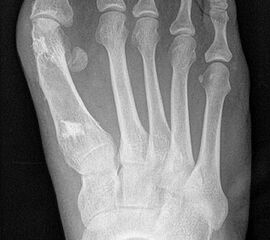

1) Rezidiv bei falschem operativem Verfahren:

Die Röntgenaufnahmen (Abbildung 1) zeigen den Fuß einer 34 jährigen Patientin nach Exostosenabtragung. Der erhöhte intermetatarsale Winkel wurde durch eine alleinige Abtragung der Exostose nicht reduziert. Als weiterer Risikofaktor für ein Rezidiv liegt ein pathologischer Gelenkwinkel vor. Der intermetatarsale Winkel von 18 Grad kann durch eine basisnahe Osteotomie gut korrigiert werden. Da durch die gleichzeitige distale Korrektur des Gelenkflächenwinkels mithilfe einer Reverden-Green Osteotomie ein Längenverlust von ca. 2-4 mm einhergeht, bot sich als proximales Korrekturverfahren die basisnahe Open-wedge Osteotomie an, um bezüglich der Länge des Metatarsale I neutral zu bleiben (Abbildung 2). Die Kombination zweier verkürzender Verfahren (z.B. Lapidus und Reverden-Green) würden zu einem sehr kurzen ersten Strahl führen, mit dem Risiko einer Transfermetatarsalgie. Übersteigt die Verkürzung des Metatarsale I 2 mm, steigt das Risiko für die Entwicklung einer Transfermetatarsalgie deutlich an 8. Die durchgeführte Revision zeigt eine gute Stellung des 1. Strahls bei zentriert stehendem Gelenk.